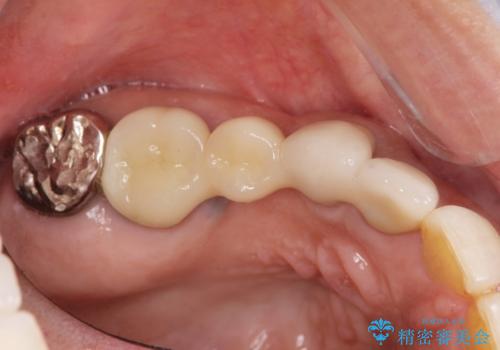

ブリッジによる補綴を行うことで周囲の歯の噛み合わせも改善ししっかりと噛むことができるようになりました。